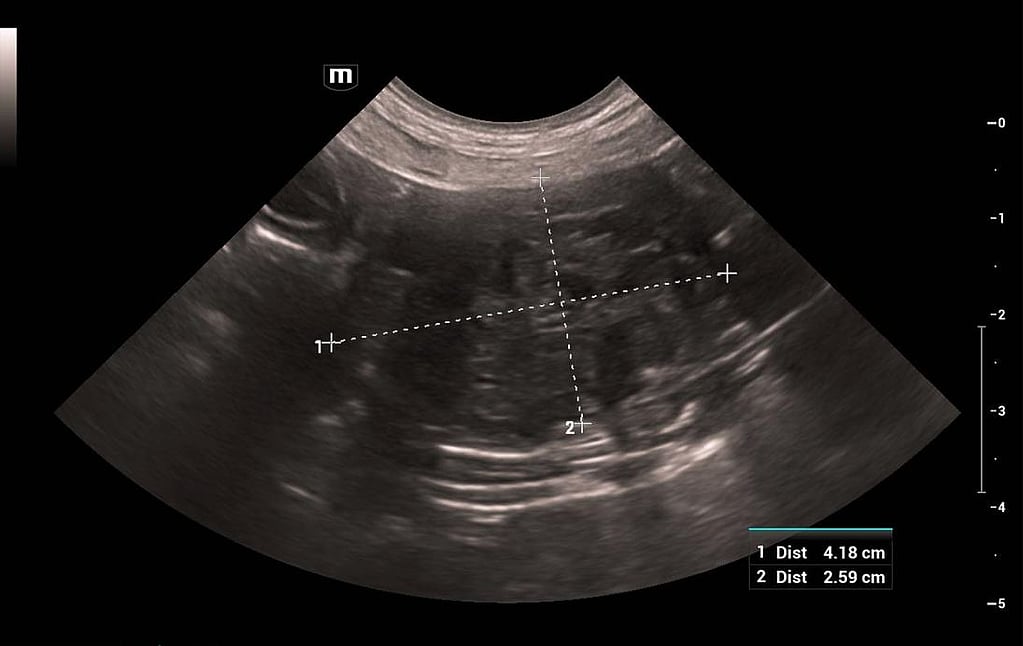

Tijdens het lichamelijk onderzoek werden tachycardie, een pijnlijk abdomen, cryptorchidie en tekenen van feminisatie (dunne vacht, prominente tepels en afhangend preputium, zie foto 1) vastgesteld. De patiënt kreeg een intraveneuze toediening van methadon waarna een echografie van het abdomen werd uitgevoerd. In het caudale deel van het abdomen werd een ovale, regelmatige, heterogene, hypo-echogene massa waargenomen (foto 2). Kleurendoppler toonde een ondermaatse doorbloeding van de massa aan. Aangezien de hond cryptorch was, werd de massa gediagnosticeerd als een abdominale neoplastische getorteerde testikel. De scrotale testikel was eerder atrofisch. Vervolgens werd een bloedonderzoek uitgevoerd. Uit de resultaten van de hematologie kon afgeleid worden dat de patiënt pancytopenie had. Deze resultaten deden vermoeden dat de cryptorche testikel een sertoliceltumor bevatte.

Foto2